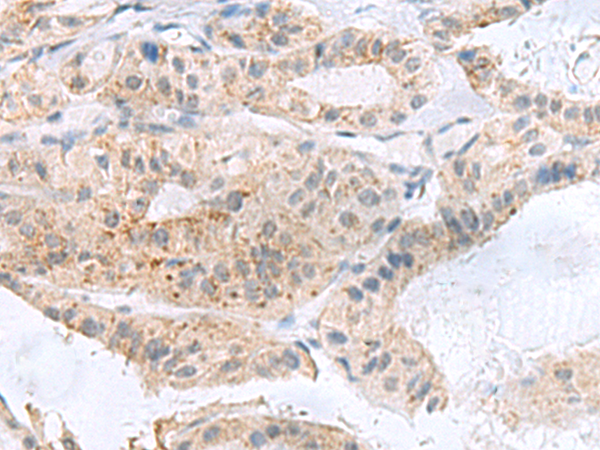

IHC positive control:

Human liver cancer and Human thyroid cancer

IHC Recommend dilution:

100-300